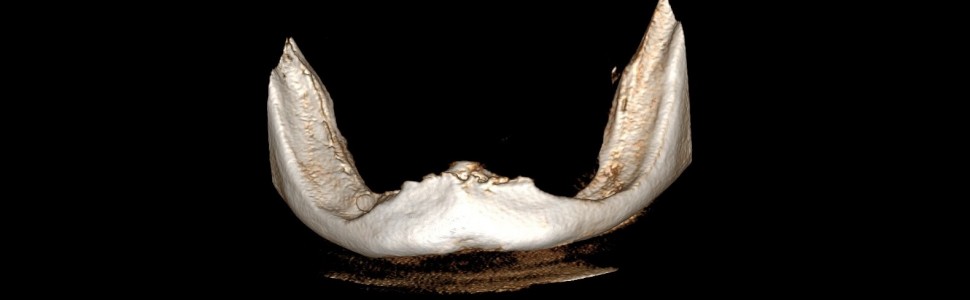

Bezzębie istotnie wpływa na jakość życia pacjenta. Wieloletnie użytkowanie całkowitych protez osiadających ogranicza możliwości przyszłego leczenia implantoprotetycznego. W artykule opisano przypadek 75-letniej pacjentki, u której zaplanowano leczenie z wykorzystaniem protezy typu overdenture opartej na implantach w żuchwie. Ponadto omówiono zalety leczenia protezami opartymi na implantach w porównaniu z zastosowaniem protez osiadających.

Edentulism significantly affects the quality of life of the patient. Long-term use of dentures limits the possibilities of future implant-prosthetic treatment. The article describes the case of a 75-year-old female patient who was scheduled for treatment with an overdenture based on implants in the mandible. In addition, the advantages of treatment with implant-supported dentures in comparison with the use of traditional dentures are discussed.